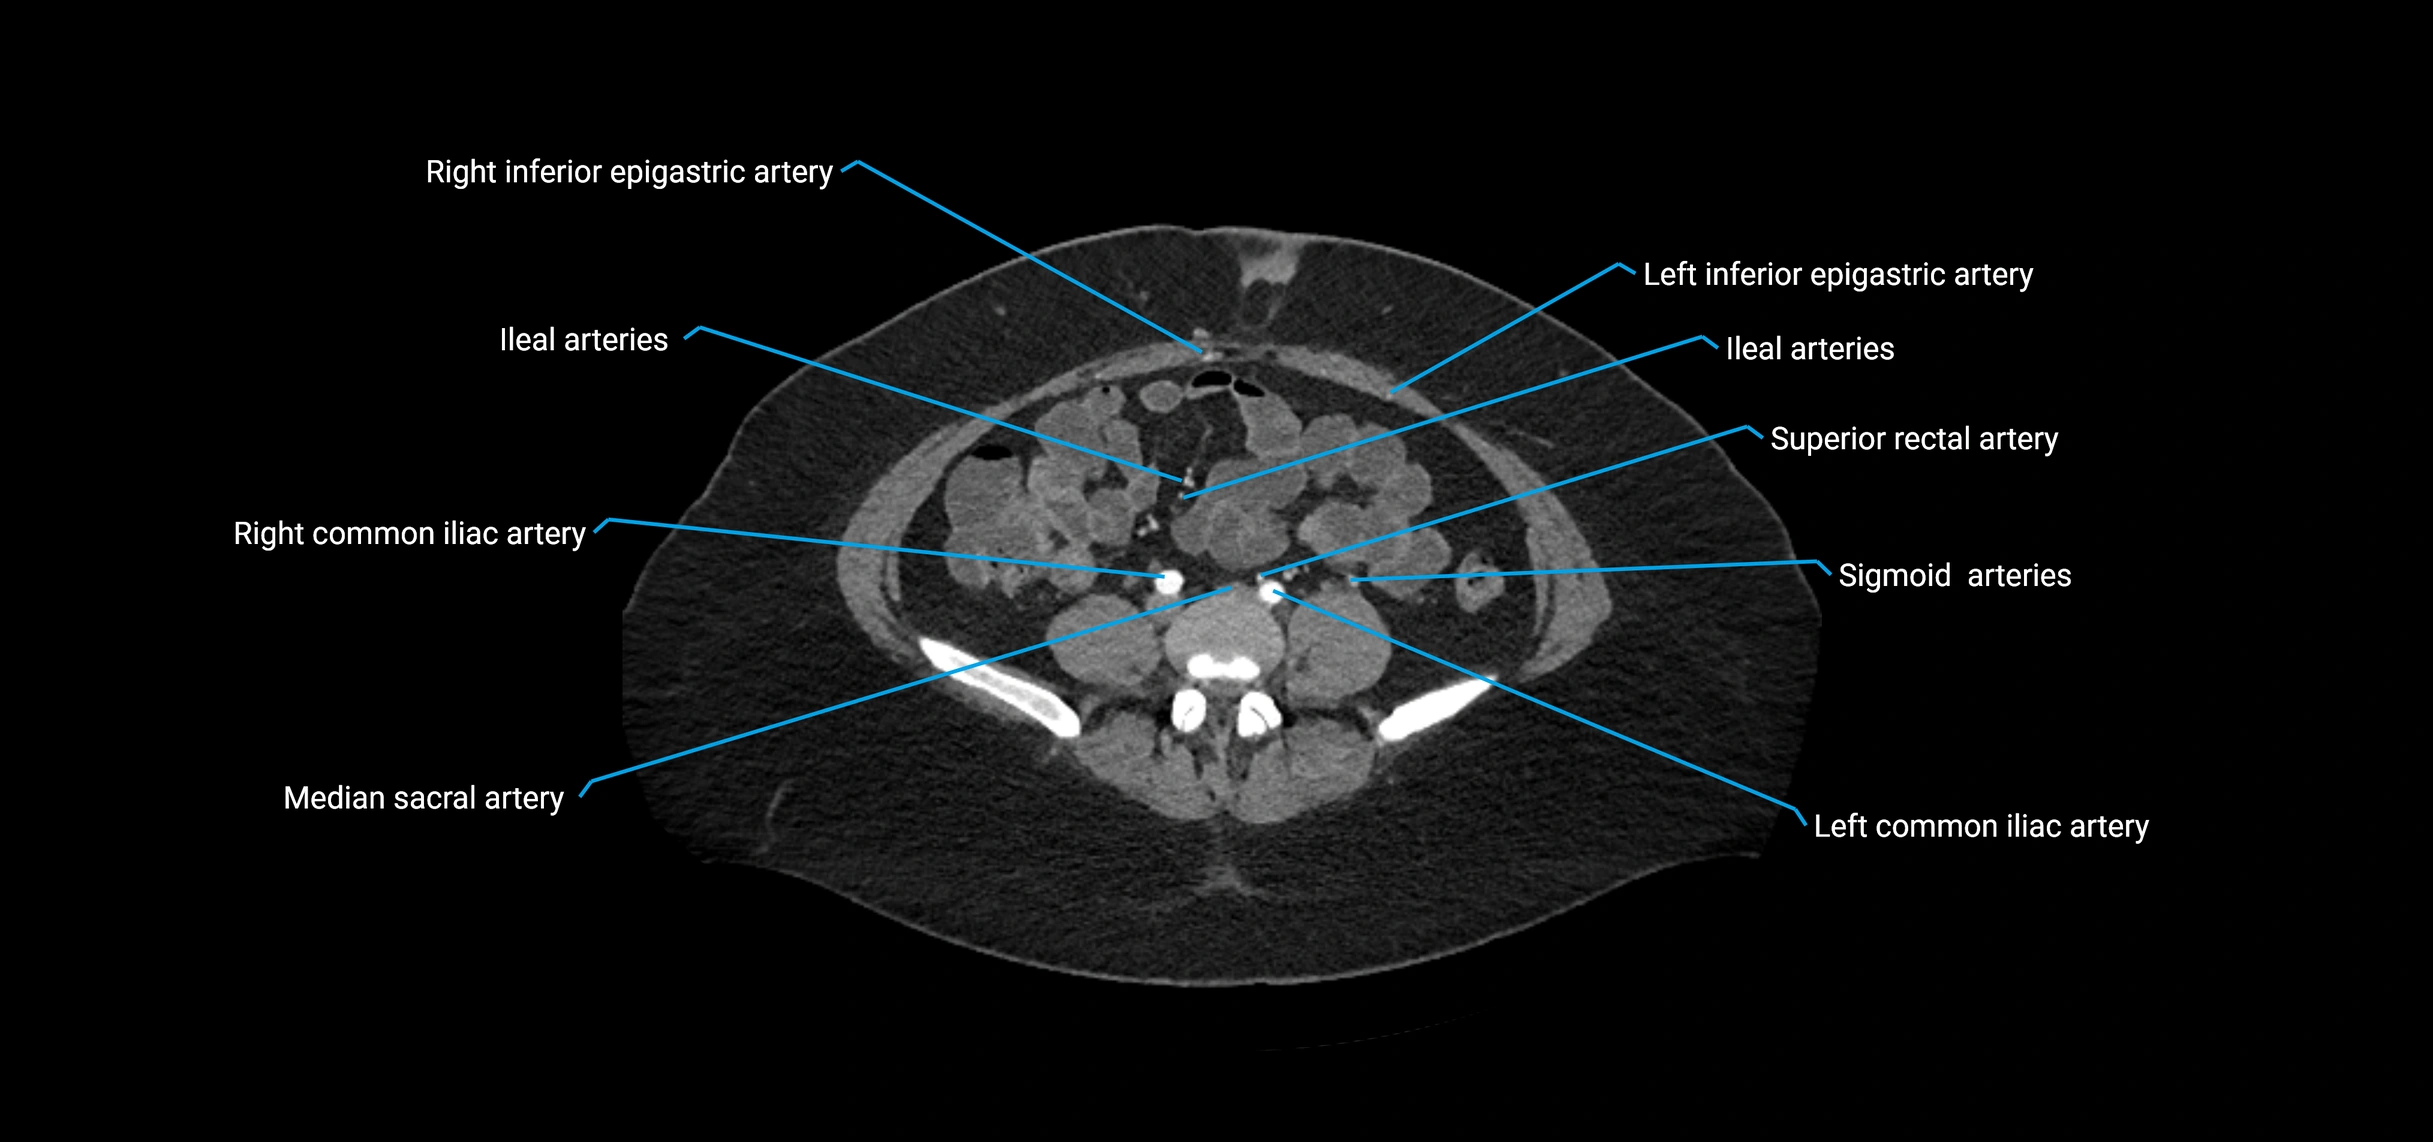

Branches

• Unpaired visceral branches: celiac trunk, superior mesenteric artery (SMA), inferior mesenteric artery (IMA)

• Paired visceral branches: middle suprarenal arteries, renal arteries, gonadal arteries (testicular or ovarian)

• Parietal branches: inferior phrenic arteries, lumbar arteries, median sacral artery

• Terminal branches: right and left common iliac arteries

CT Appearance

Contrast-enhanced CT (CTA):

• Gold standard for abdominal aortic imaging

• Provides excellent detail of lumen, wall, aneurysm, thrombus, and branch vessels

• Multiplanar and 3D reconstructions help in aneurysm measurement, stent graft planning, and dissection evaluation

CT images

image